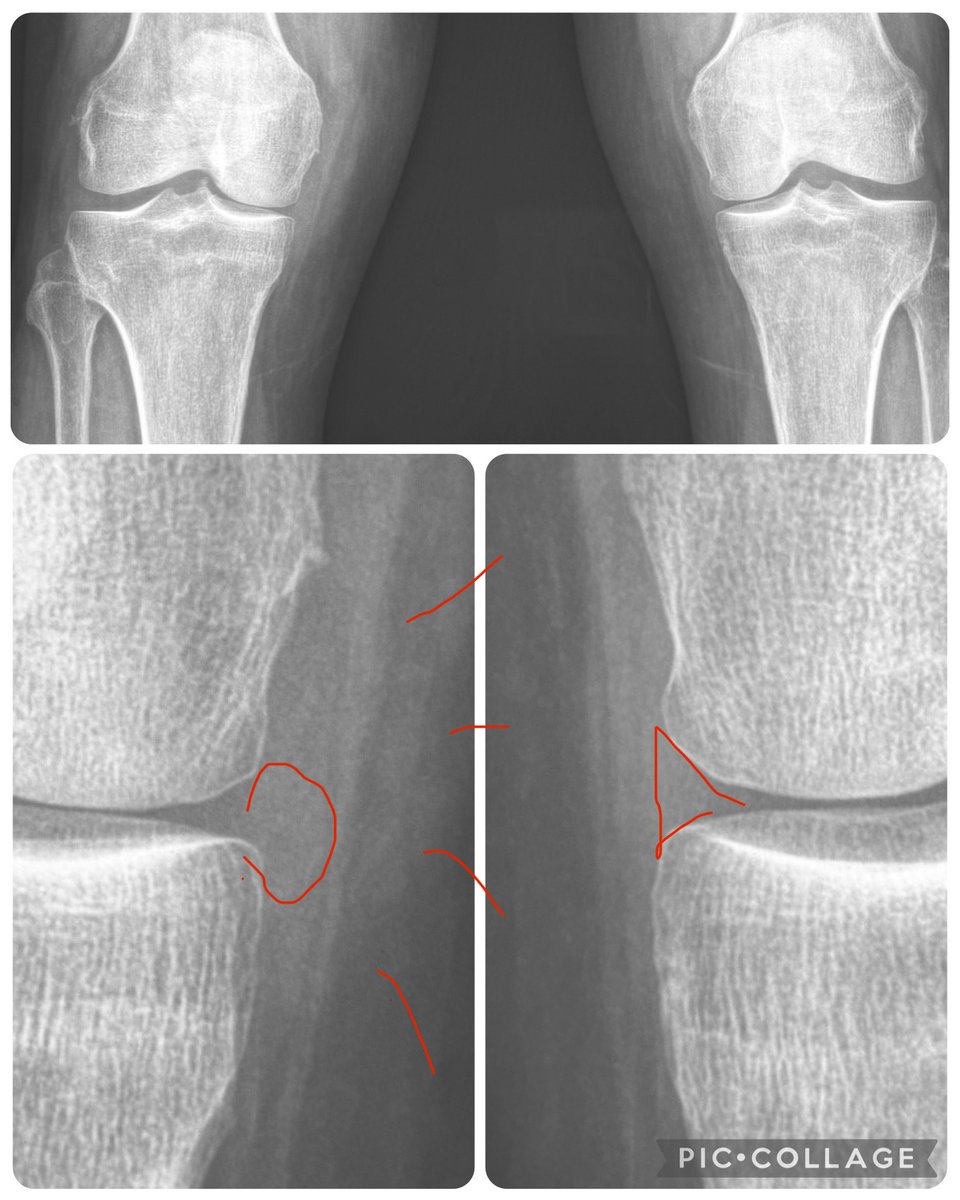

Before attributing ‘joint space narrowing’ at the knee to arthritis, take a look at the meniscus (yes, you can faintly see menisci on radiographs) - often the narrowing is due to meniscal extrusion, which in turn is related to meniscal tear.